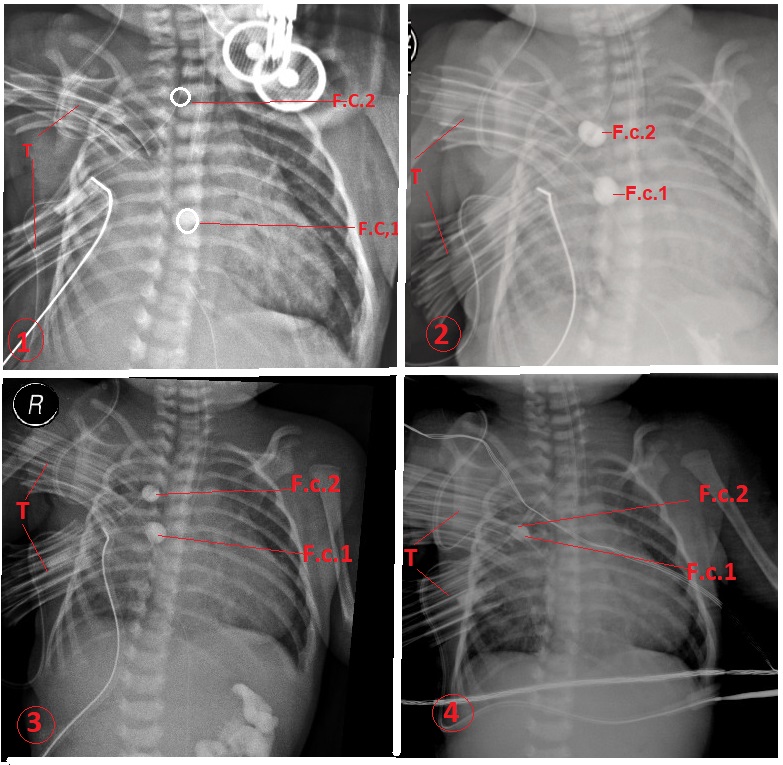

Serial chest x-rays (1-4) showing the progress of the balloons of the catheters.

The traction on catheters helped in the elongation of both esophageal ends. The traction was achieved by the daily insertion of small tubes between the exit site of the catheters and the fixation point of the catheters (Fig. 2). Repeated daily chest x-ray showed the progress of elongation of esophageal ends as measured by the distance between contrast filled Foley catheter bulbs (Fig. 3). The close approximation was achieved on the 8th and 10th day, respectively. By that time, a second thoracotomy was performed, the Foley catheters were removed, a rim of tissue of the lower esophageal segment at the site of the purse-string sutures was resected, and an end to end esophageal anastomosis was performed using interrupted 5-0 Vicryl™ sutures over a trans-anastomotic nasogastric tube. An oral contrast study performed on the 7th postoperative day showed the free passage of contract, thus oral feeding was established gradually. Both infants recovered well and had intact esophagus. Both had gastroesophageal reflux postoperatively. Both are thriving well on a follow-up of 7 and 12 months, respectively.